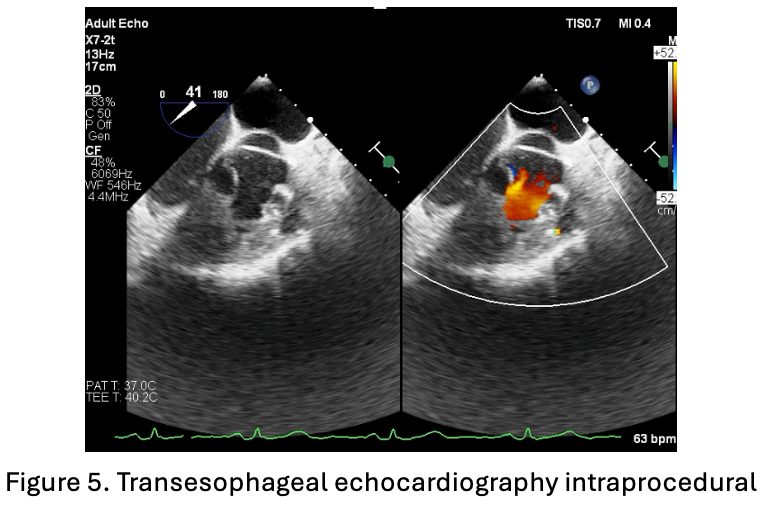

An 8F sheath was inserted into the femoral vein and an arterial line was placed in the femoral artery. Intraoperative transesophageal echocardiography (TOE) showed a very tight right ventricular outflow tract (RVOT) measuring 23.7 mm in length, with a left ventricular ejection fraction (LVEF) of 51.7% by Simpson¡¯s method. RVOT angiography performed using a 3.5/5F Guiding JR catheter confirmed narrowing at the RVOT segment.

A soft hydrophilic 0.035-inch wire was directed into the RVOT, advanced distally to the right pulmonary artery, then exchanged for a super stiff 0.035-inch wire. An Armada vascular balloon 7.0x60 mm was positioned in the RVOT and inflated to 12 atm for ten cycles. An Omnilink vascular stent was deployed in the RVOT and inflated to 12 atm. Due to the patient¡¯s late presentation, a second identical stent was placed at the same location. Following the procedure, LVEF improved to 64.7%, and aortic oxygen saturation increased from 86% to 94%.